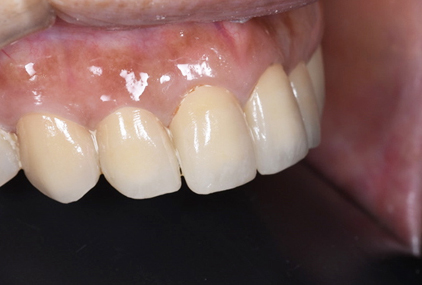

途中経過

患者様の主訴は、「保険の黄色くなったかぶせ物を白くしたい」でした。

保険のかぶせ物は、プラスティックで白い部分を作成するので、どうしても経年劣化で黄色く変色してきます。また、この患者さんは、横から見るとその歯がだいぶ前に出ていたために、少し出っ歯にも見えていました。

保険のかぶせ物を除去して、仮歯に置き換えて、その後プロビジョナルと言われる最終的な仮歯をセットして歯肉の状態を確認します。問題がないことを確認してから、最終的な型採り試適の後に最終的なセラミックのかぶせ物をセットしました。